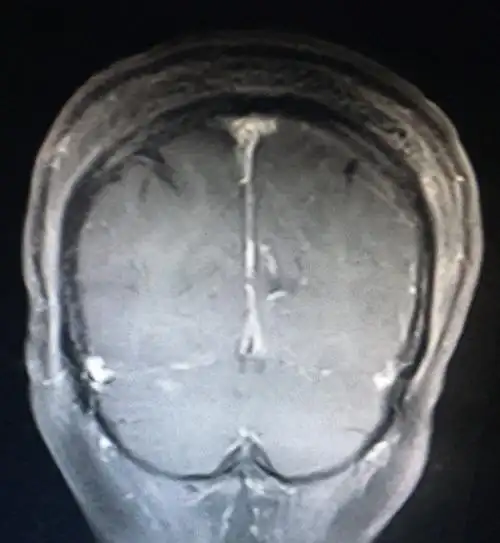

脑膜瘤一例 - 好大夫在线

枕部大脑镰良性脑膜瘤 - 好大夫在线

右侧顶叶窦镰旁脑膜瘤一例

松果体区脑膜瘤一例神经肿瘤系列十六浙二神外周刊第294期